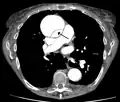

| Stanford type B dissection of the descending part of the aorta (3), which starts from the left subclavian artery and extends to the abdominal aorta (4). The ascending aorta (1) and aortic arch (2) shown in the image are not involved in this condition. | |